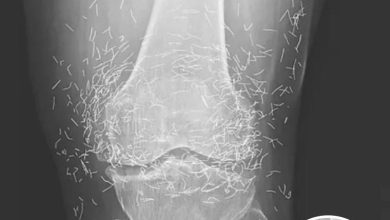

Doctors Stunned After Looking At This X-Ray Of Woman Suffering Joint Pain

A routine X-ray revealed an unexpected surprise when doctors examined the knees of a 65-year-old woman suffering from severe joint…